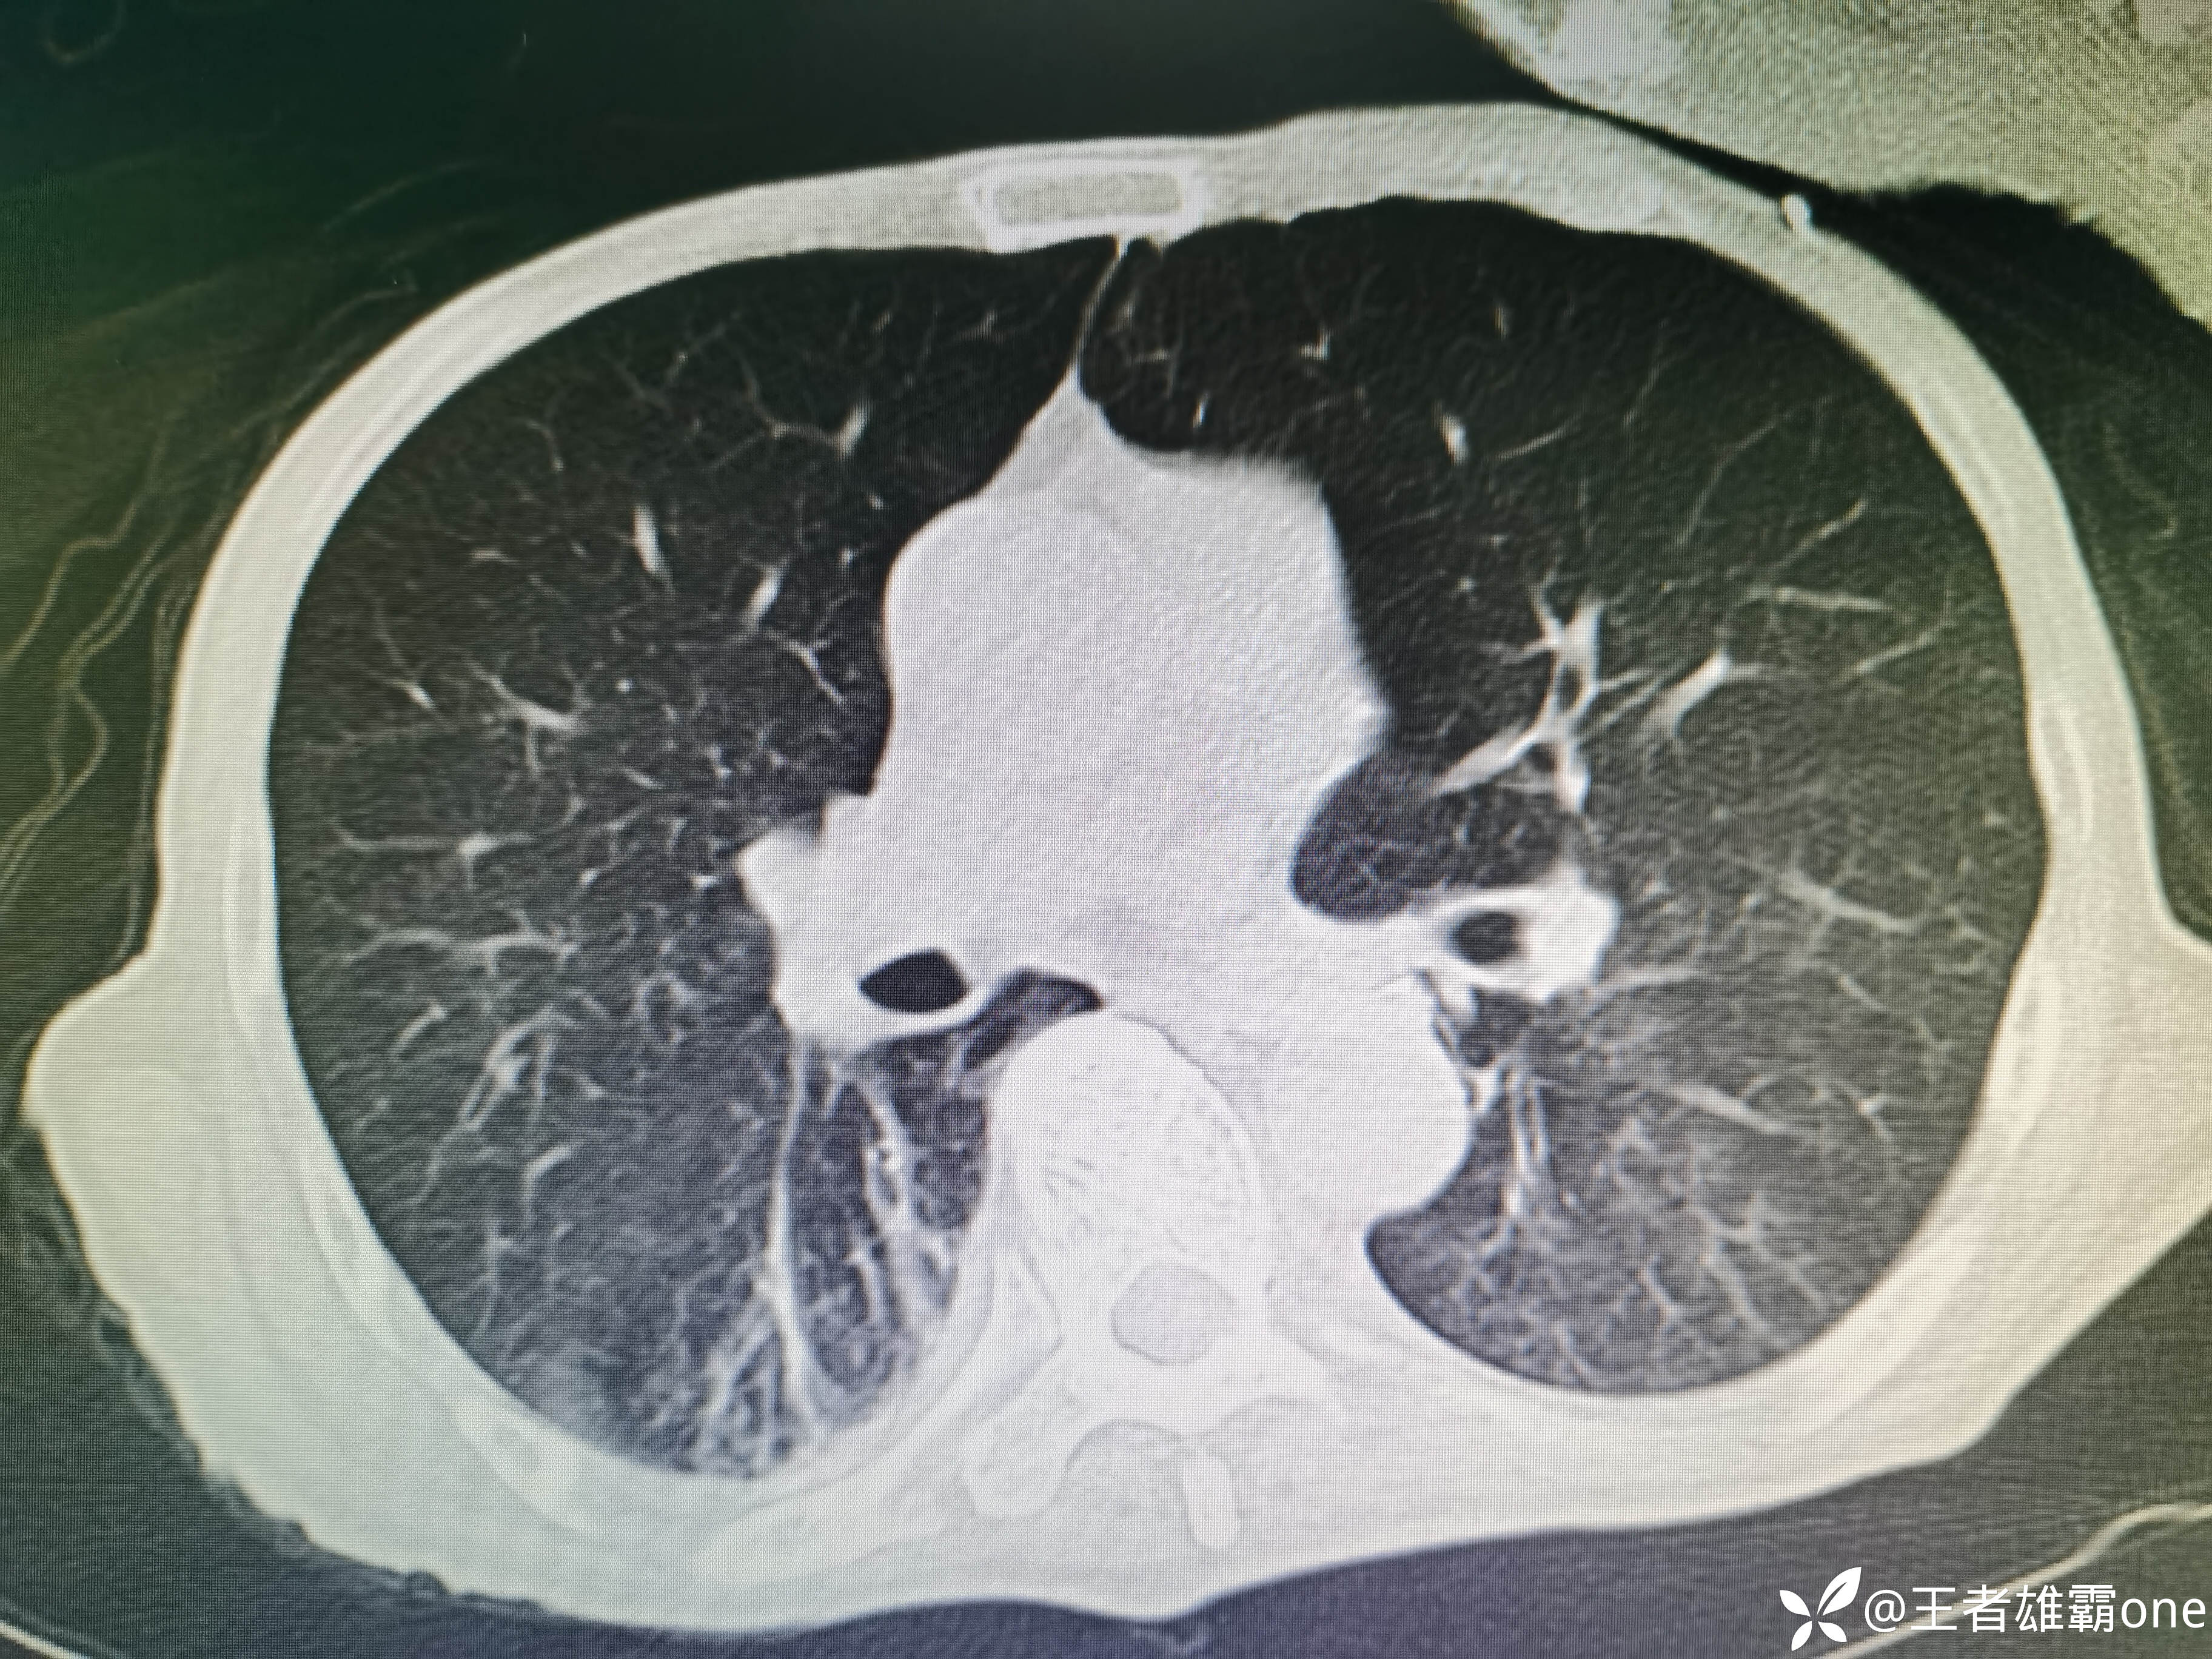

入院时胸部CT:

具体图片: